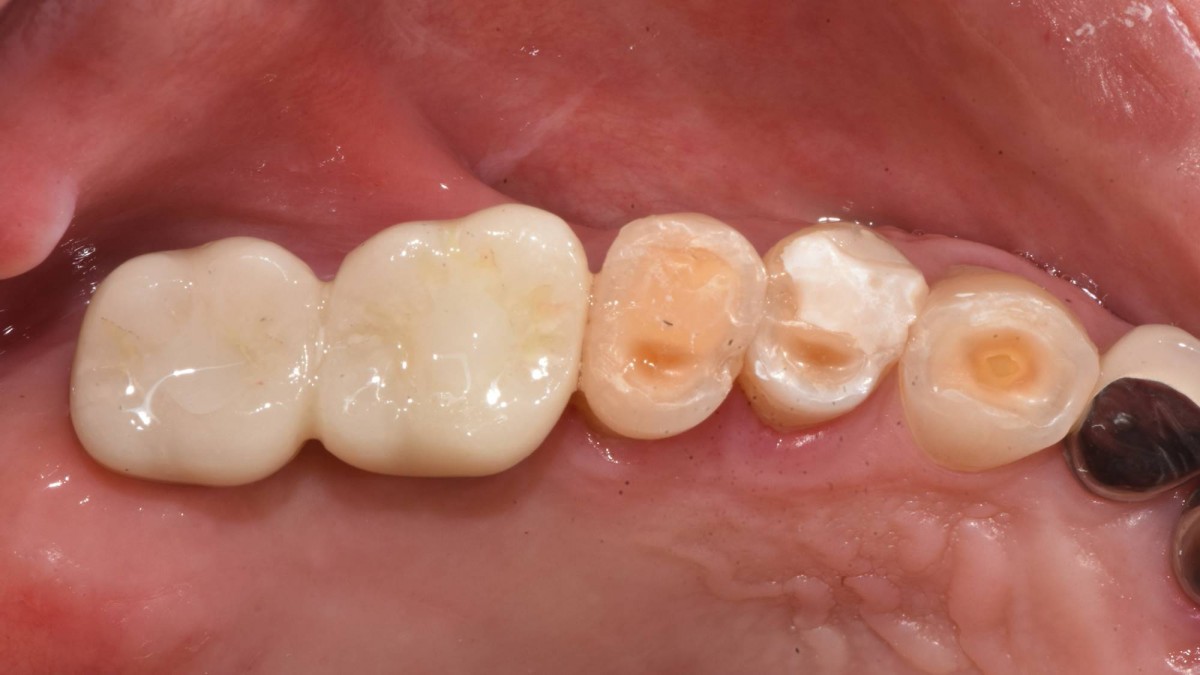

Socket Lift and Implant Placement in the right maxilla.